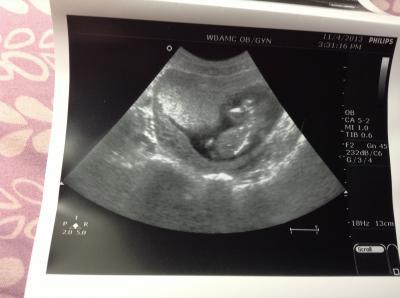

Guten morgen Mädels, Hatte ja gestern Abend auch einen Termin hier in el Paso und bin nun wach und wollte mal berichten! Bei mir ist es ähnlich wie bei Katja, sie haben nur die Herztöne kontrolliert, gewogen und den Blutdruck gemessen, keinen abstrich gemacht oder den Muttermund abgetastet! Ist irgendwie komisch das das auch so funktionieren kann! Mein Mann war aber extra mit, weil er sein Baby das erste mal sehen wollte und dann hat sie extra für ihn noch einen Ultraschall gemacht! Sie hat zwar nichts gemessen, war aber alles dran und Papi hat es dann auch noch zugewunken! War sehr bewegend! Wenigstens habe ich Medikamente gegen die Migräne und gegen Übelkeit bekommen! Der nächste Termin ist dann diesmal schon in 4 Wochen, dann denke ich aber ohne Ultraschall! Habe aber schon einen für Ende Dezember für ein großes organscreening bekommen! Dann wird auch das Geschlecht ermittelt! Es heißt also noch ein bisschen gedulden! Und im Januar heißt es dann endlich home Sweet home gemany Lg claudi

Bild zu Fa Bericht - Forum für Mai - Mamis

Schön dass alles gut ist !! Das Bild ist gut geworden, ich hab grad das Gefühl das geht alles voll schnell. Ich hab heute nen Termin zum Organultraschall in der Klinik gemacht für den 11.12.13 super Datum gell ;-) ich hoffe dass dann das Kindlein kooperativ ist und sich outen mag. LG Mila